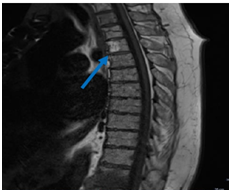

A 78-year-old woman with a history of a biological aortic prosthesis, implanted in 2016, and atrial fibrillation was admitted to the emergency department due to progressive worsening of low back pain for 3 weeks with irradiation to the lower limbs and severe gait limitation. The pain was poorly responsive to analgesics. She had no history of trauma. At the physical examination, she presented apyretic, tachycardic, sleepy, with degree III/VI systolic murmur without irradiation and palpation pain in thorny apophyses in D12 to L4. No sensory or motor deficit. Blood analyses revealed Hb: 9.9mg/dL, leukocytosis 10,800 with neutrophilia 83%, Protein-C-reactive 11mg/dL, VSG: 131mm/h, Cr: 2.4mg/dL, Urea 99.7mg/dL; LDH 313, CK: 506. Lumbar CT scan revealed "multiple and small millimetric osteolytic lesions in almost all of the lumbar somatic bodies and the left lateral slope of the upper S1 platform, some with rupture of the cortical bone." After hospital admission, there was a worsening of the general state of the patient with sudden onset of fever, tachycardia, and exacerbation of severe intensity low back pain associated with paraparesis and Janeway cutaneous lesions in the plantar region of the foot (Figure 1). There were no signs of acute heart failure. She performed an ECG with atrial fibrillation and a CT-EC without acute ischemic changes. Due to the high suspicion of endocarditis, blood cultures were collected, and a transesophageal echocardiogram was performed, revealing vegetation on the ventricular side of the biological prosthesis in aortic position without obstruction and without associated regurgitation or local complications (Figure 2). Given the new findings, it empirical antibiotic therapy with vancomycin and gentamicin was initiated and a lumbar spine magnetic resonance imaging was performed that showed “D12-L1 reduction in inter somatic height, vertebral platform irregularities, disc edema and diffuse alteration of the bone matrix signal of the D12 and L1 vertebral bodies (T2/STIR and hypoT1) with marked enhancement, translating inflammatory/infectious changes in the context of spondylodiscitis” (Figure 3) Hemocultures were positive for S. epidermidis methicillin-resistant.